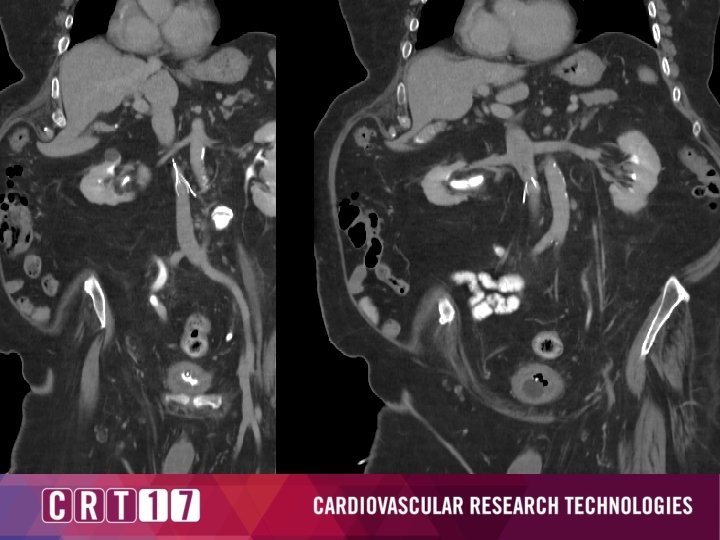

Device Related Complications